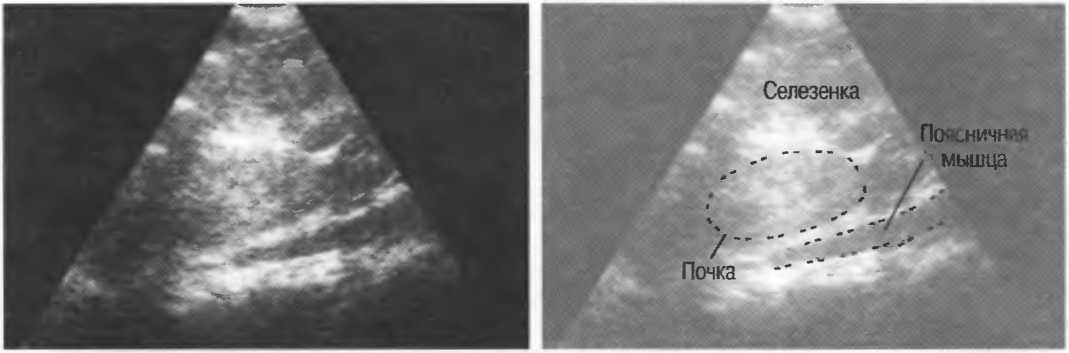

Затухание

Ткани тела поглощают и рассеивают ультразвук по-разному. Высокие частоты поглощаются и рассеиваются (гасятся) в большей степени, чем низкие. Поэтому, чтобы достичь более глубоких тканей, необходимо использовать более низкие частоты, так как менее вероятно, что эти волны затеряются при прохонодении через ткани. На практике оптимально использовать частоту около 3,5 МГц для глубокого сканирования у взрослых и частоту 5 МГц и выше для исследования более худых пациентов или детей. Частота 5 МГц и выше используется для исследования поверхностных органов у взрослых.

Выбор соответствующего датчика

Наилучшим датчиком для общей практики является конвексный датчик с частотой 3,5 МГц с фокусировкой на расстоянии 7-9 см. Если такого датчика нет, необходимо наличие линейного секторного датчика с частотой 3,5 МГц. При необходимости исследования детей и худых взрослых желательно дополнить набор датчиком с частотой 5 МГц с фокусировкой 5-7 см.

1. Ультразвуковые исследования в акушерстве. Для общих исследований в акушерстве используется линейный или конвексный датчик с частотой 3,5 или 5 МГц с глубиной фокусировки на 7-9 см. Если закупается только один датчик, выбирайте датчик с частотой 3,5 МГц. Датчик с частотой 5 МГц предпочтителен на ранних сроках беременности. В поздние сроки беременности лучше использовать датчик с частотой 3,5 МГц.

2. Ультразвуковые исследования в общей практике. Если проводятся исследования в верхней части живота и таза у взрослых, в том числе и акушерские исследования, предпочтительнее выбор секторного или конвексного датчиков с частотой 3,5 МГц с глубиной фокусировки на 7-9 см.

3. Ультразвуковые исследования в педиатрии. Для детей необходим датчик с частотой 5 МГц с глубиной фокусировки на 5-7 см. При исследовании мозга новорожденного используется секторный датчик с частотой 7,5 МГц с глубиной фокусировки на 4-5 см (этот датчик также используется для исследования яичек и структур шеи у взрослых).